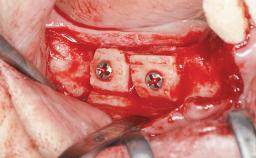

Shell Technique for Horizontal and Vertical Maxillary Bone Augmentation in a Partially Edentulous Patient with Aggressive Periodontal Disease

A 46-year-old woman was referred for treatment whose main complaints were mobility of her fixed partial dentures (right maxilla and left mandible) and periodontal bleeding during function. She also reported having taken systemic antibiotics to treat recurrent swelling in the area of the upper left molars. The patient had not seen a dentist for at least 2 years. She did not smoke and had no history of major systemic disease other than two minor orthopedic procedures some years back. The first-visit examination revealed poor plaque control, tooth mobility, periodontal disease, and a residual dentition widely associated with deep periodontal pockets.

Bone Augmentation Horizontal|Staged|Vertical

Augmentation Materials Autogenous chips|Autogenous block(s)|Xenogenous